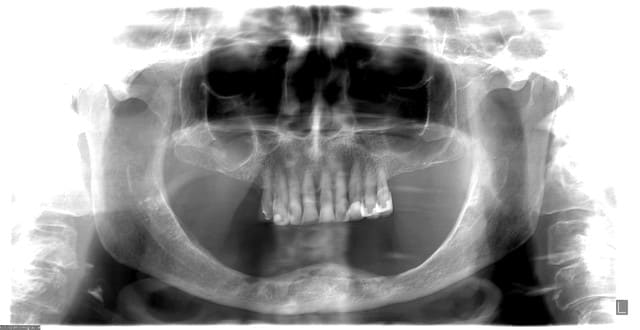

Bonjour, une patiente de 83 ans voudrait se debrasser de sa prothese amovible (elle en a deja fait plusieurs) qui n'est oas du tout stable. en fait vous pouvez le constater sur la panoramique jointe. il n'y pas de crete pour stabiliser . elle n'a aucun probleme se sante. dans ce cas la solution qui s'impose c la prothese implanto-portee?

- 2 implants avec piliers Locator, mais la je crains la bascule antero-posterieure.

certains me déconseillent de poser 2 implants, (et c de l'acis du chirurgien aussi) et penchent pour la pose de 4 implants avec les Locator